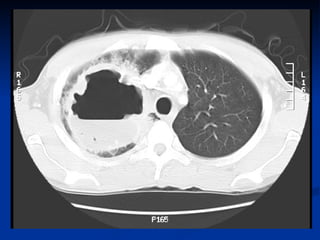

   It manifests radiographically as a cavity with an

air – fluid levels.

1.   CXR, CT CHEST

definition  A localized area of destruction of lung parenchyma in which infection by pyogenic organisms results in tissue necrosis & suppuration .  It manifests radiographically as a cavity with an air – fluid levels.